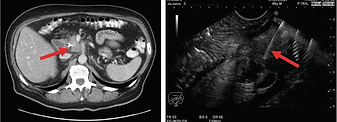

Pomocne w diagnostyce: USG (B超), tomografia komputerowa (CT), rezonans magnetyczny (MRI), biopsja wątroby, badania biochemiczne i immunologiczne krwi.

Mammografia (zdjęcie rentgenowskie) – widoczny nieregularny, gęsty cień guza z poszarpanymi brzegami, często z mikrokalcynacjami, pogrubienie skóry piersi, retrakcja brodawki.

USG piersi (B-mode) – obecność zmian ogniskowych o charakterze litym.